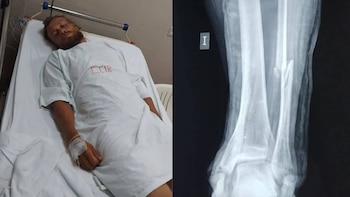

Ciclista ruso atropellado en Áncash enfrenta riesgo de perder la movilidad y requiere cirugía urgente tras accidente vial

Nikita Ipatov, turista que recorre el mundo en bicicleta, sufrió una grave fractura de tobillo tras ser atropellado por un vehículo que se dio a la fuga